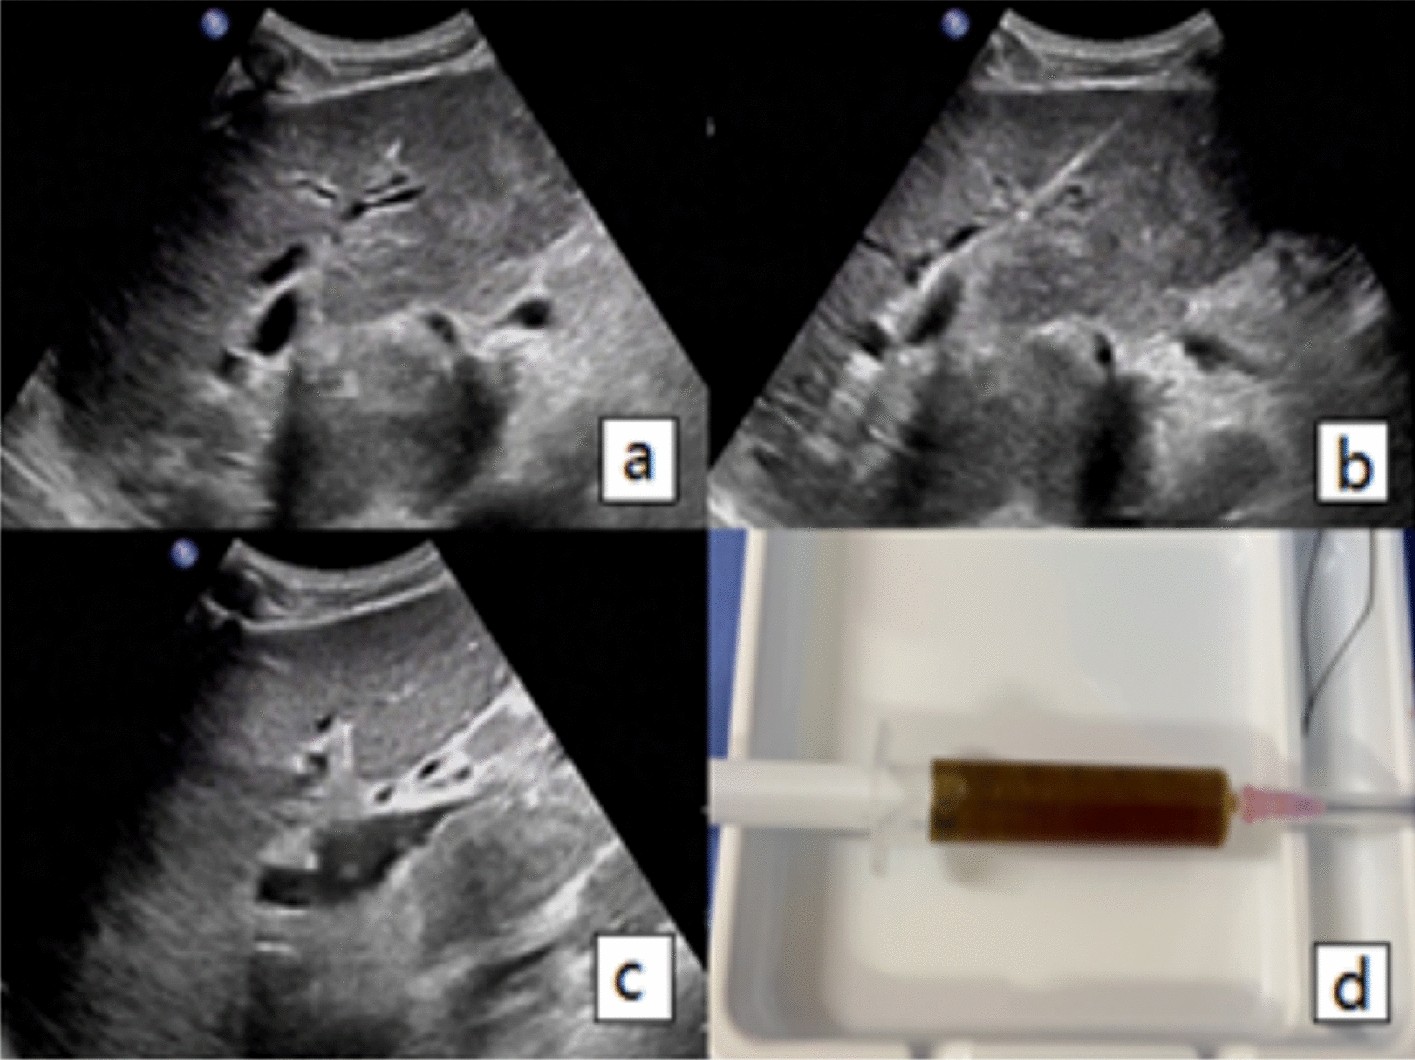

Figure 1

(a) Ultrasound image of a 67-year-old male patient with ampullary carcinoma who underwent PTBD, and the diameter of hepatic segment bile duct was 5mm. (b) Shows a guide wire being inserted into the hepatic S3 bile duct. (c) Shows an 8F drainage tube being inserted along the guide wire. (d) Shows the brown turbid bile fluid being drawn out.